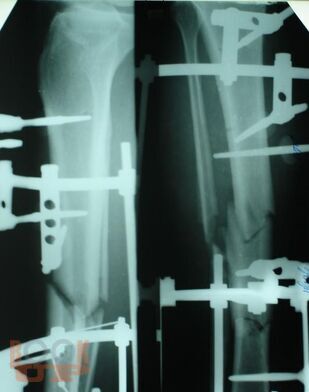

Учебно-методическое пособие содержит необходимую информацию для врачей по вопросам оказания специализированной помощи пострадавшим с тяжелой травмой костей нижних конечностей. Подробно освещены вопросы тактики оказания специализированной и высококвалифицированной помощи пострадавшим с тяжелыми монолокальными, множественными и сочетанными переломами костей конечностей в зависимости от периода развития травматической болезни. Отмечено, что в настоящее время оперативное лечение является основным при лечении переломов костей конечностей с учетом хирургической тактики контроля повреждения. Особое внимание уделено профилактике и лечению ранних осложнений тяжелых повреждений опорно-двигательного аппарата – синдрому жировой эмболии, тромбоэмболическим осложнениям. В пособии обобщен более, чем 20- летний опыт лечения пациентов с тяжелой травмой костей конечностей.